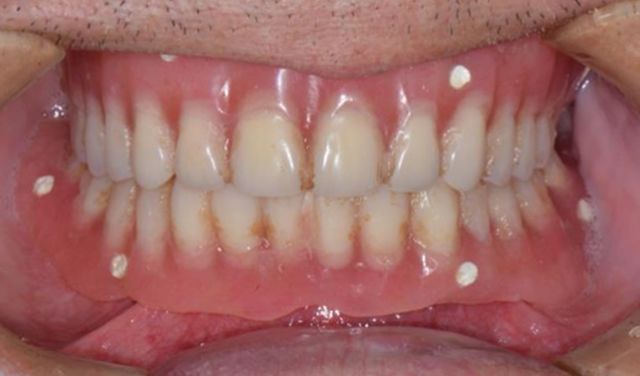

精彩案例: